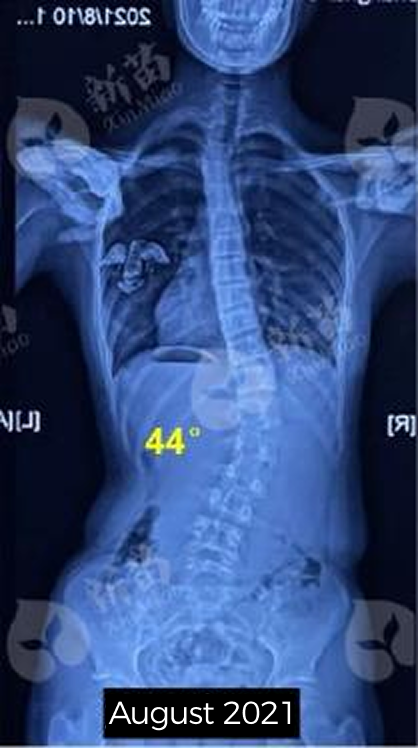

Xiaoye was diagnosed as 44°scoliosis at the age of 12. Her family went to several well-known hospitals in China. The doctor recommended surgery as soon as possible. But Xiaoye did not want surgery and still hoped an non-surgery treatment.

diagnosed with 44°of scoliosis in August, 2021